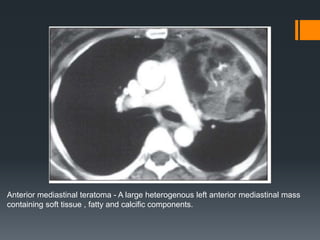

Anterior mediastinal teratoma - A large heterogenous left anterior mediastinal mass

containing soft tissue , fatty and calcific components.